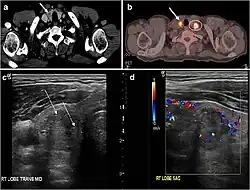

Fig. 4. A 45-year-old male patient presented with anterior mediastinal metastatic PTC lesions and occult primary on imaging. Histopathology examination of the resected thyroid gland revealed micro-foci of PTC; the largest, in the isthmus, measured 4 mm. a transverse greyscale ultrasound of the thyroid demonstrates homogeneous gland with normal echogenicity and size. No focal lesion or micro-calcifications. b Non-enhanced CT scan obtained as part of PET/CT examination shows a heterogeneous, large, relatively dense anterior mediastinal mass (white arrow) with peripheral calcification (arrowheads). Thyroid gland has normal CT appearance with no abnormal FDG uptake (not shown).[1] -

Fig. 7. A 51-year-old female patient post total thyroidectomy for PTC with elevated thyroglobulin measurement. an Axial non-enhanced CT scan of the neck at the level of the thyroid bed demonstrates a well-defined, rounded, homogenously dense soft tissue situated between the trachea and left internal jugular vein (white arrow). b Transverse ultrasound image of the neck demonstrates a well-defined, homogeneous, hypoechoic soft tissue nodule measuring 6 mm (white arrow) with no detected micro-calcifications. Biopsy showed a predominantly residual normal thyroid tissue with micro-foci of PTC.[1] -

Fig. 8. A 48-year-old male patient post total thyroidectomy with PTC recurrence. a Transverse greyscale ultrasound of the neck demonstrates a left thyroid bed heterogeneous, predominantly hypoechoic irregular lesion with calcifications (white arrow). b A spot image of iodine 123 total body scan of the neck demonstrate a focus of abnormal radiotracer uptake at the left thyroid bed (Black arrows) between the annotated markers. c Enhanced axial CT scan of the neck demonstrates an enhancing large left thyroid bed mass (white arrow) with no calcifications. The lesion exerts a mass effect on the oesophagus (black arrow) and is inseparable from the trachea.[1] -

Fig. 9. A 58-year-old male patient with persistence PTC at thyroid bed with hypervascular nodal metastasis. a–c Transverse greyscale and colour Doppler neck ultrasound demonstrate hypoehoic soft tissue in the left thyroid bed (white arrow in a). There are a heterogeneous enlarged lymph nodes at level 2 and 3 with markedly increased vascularity (white arrow in b and c). d–f Enhanced axial CT images of the neck demonstrate a 2.7 × 1.4 cm hypodense soft tissue lesion anterior to the left carotid sheath (white arrow). There are left-sided enhancing abnormal and enlarged lymph nodes at cervical level 2 and 3 (black arrows).[1]